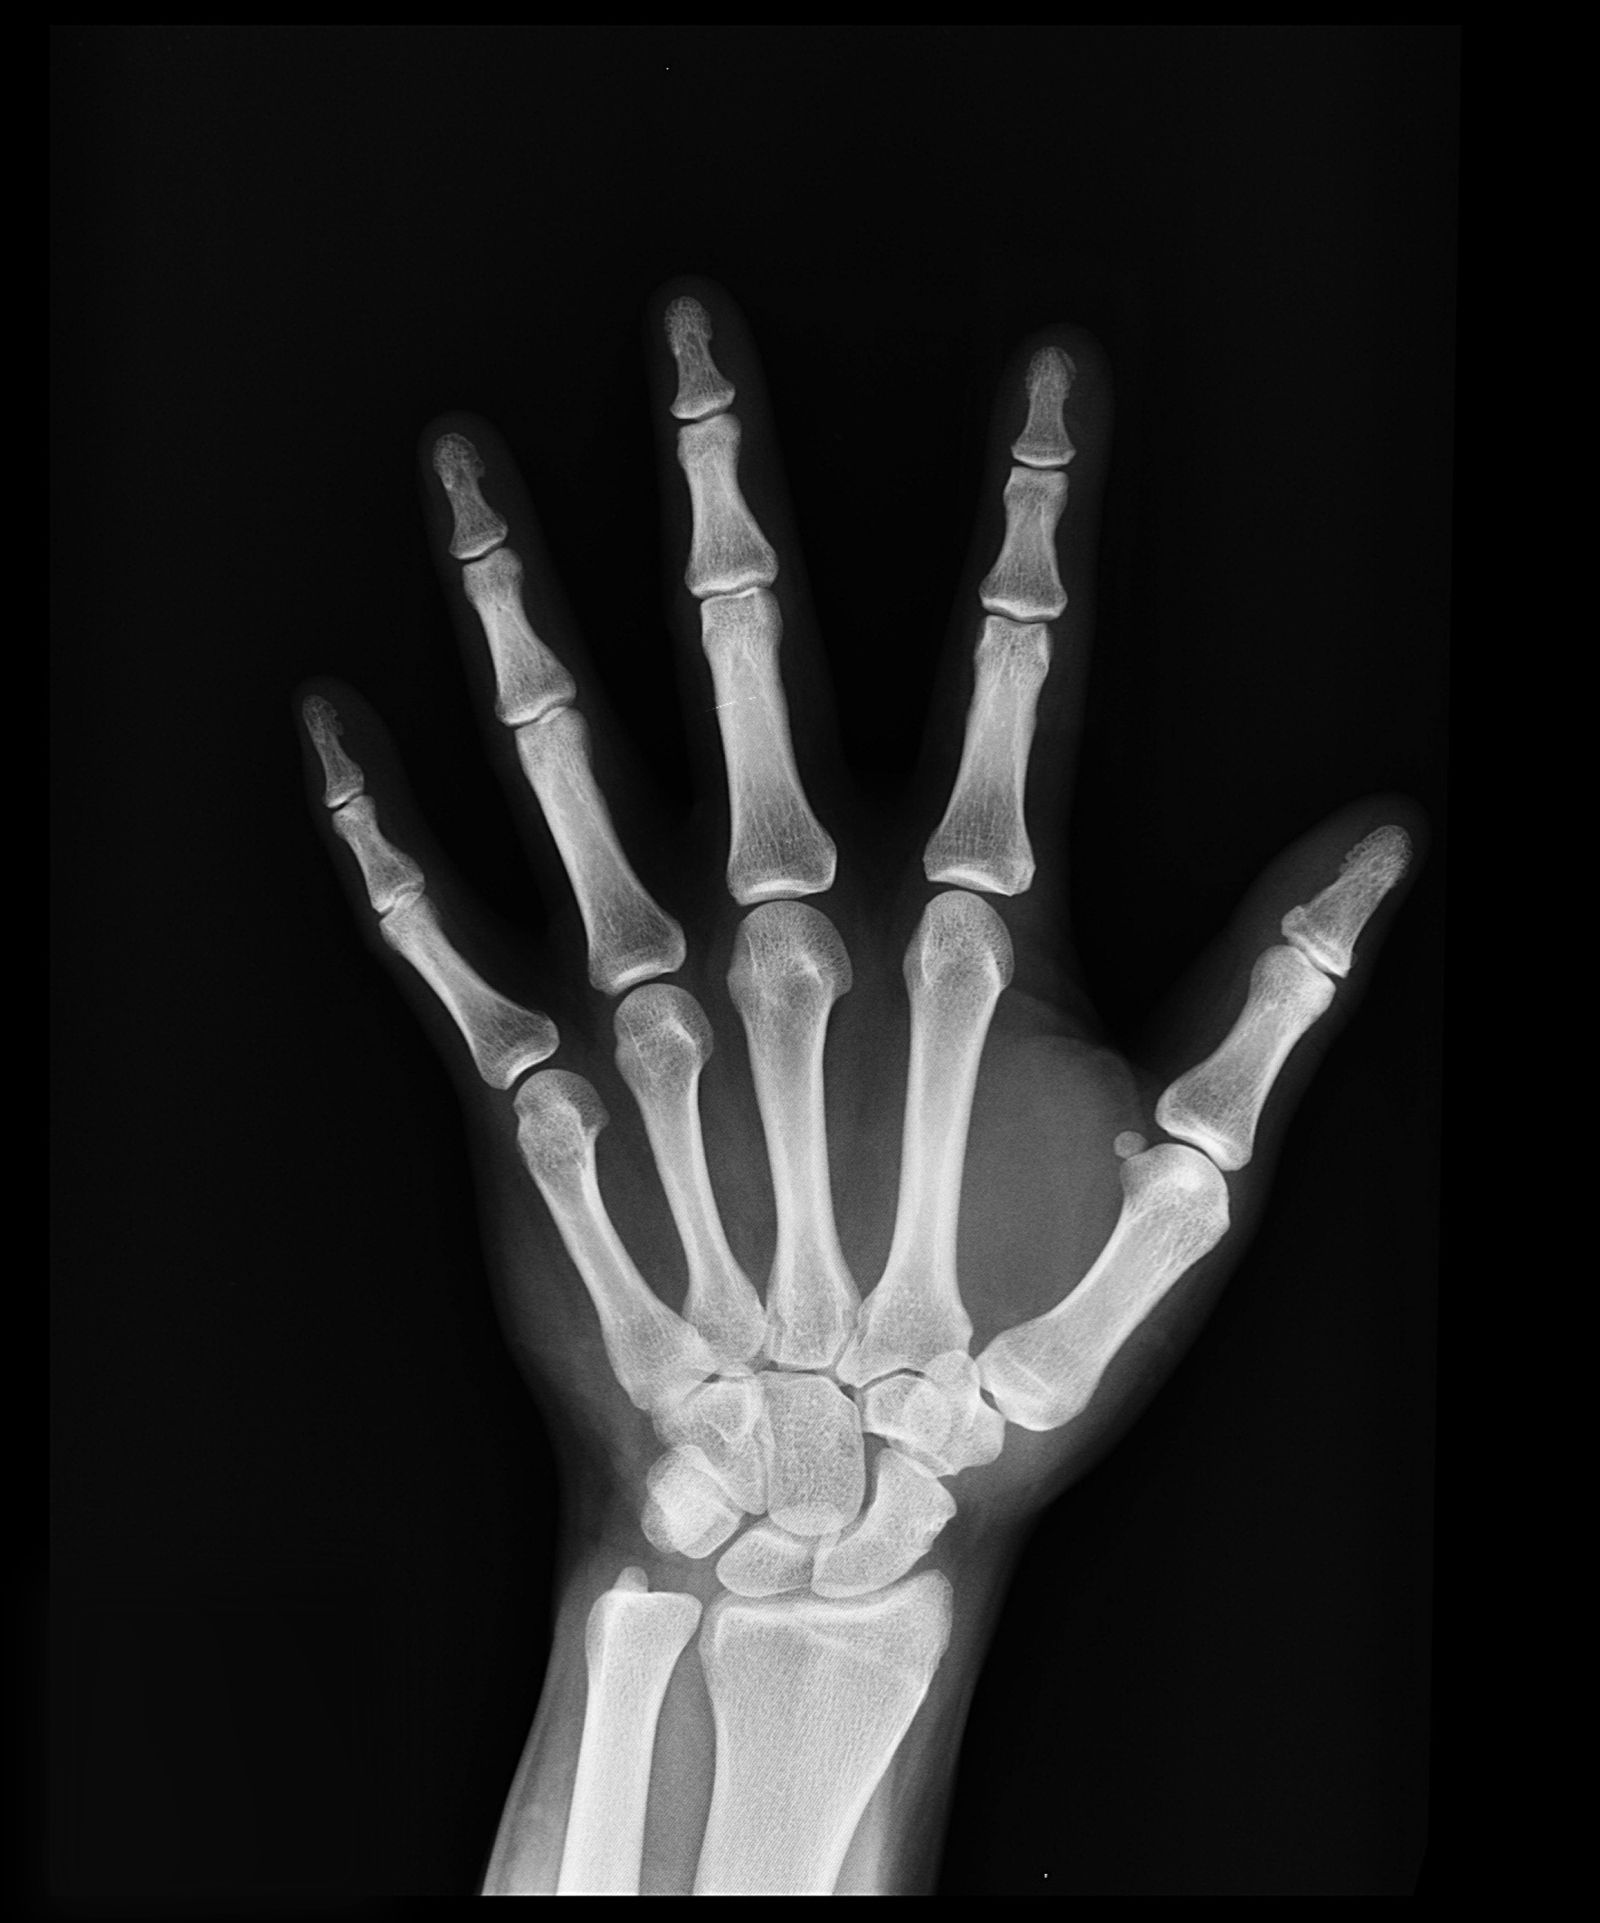

Image d'illustration Pexels